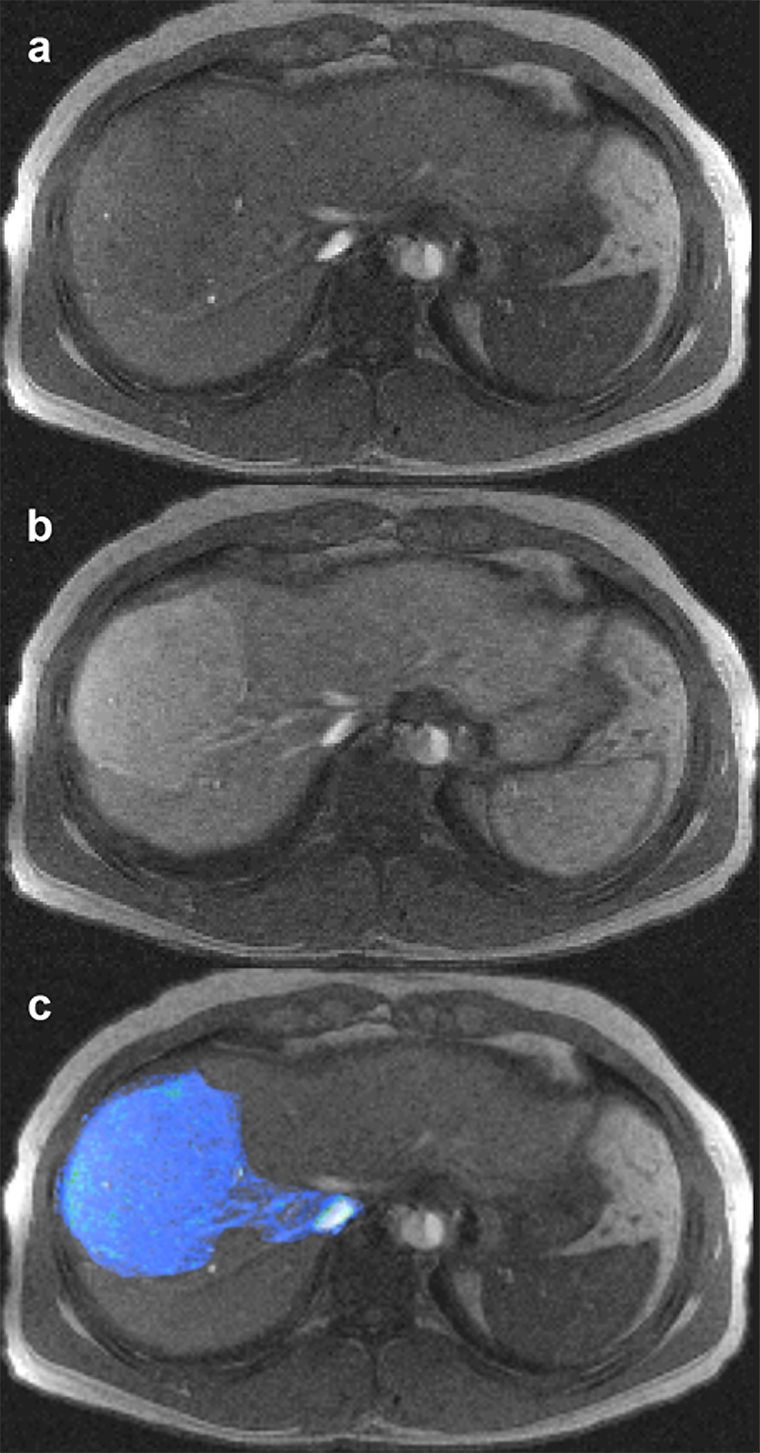

Figura 15-08:

Multichannel images: (a) plain image of a liver, (b) contrast-enhanced liver, with depiction of focal no­du­lar hyper­pla­sia, part of a dy­na­mic series, and (c) overlay (superposition) of enhanced lesion on plain liver im­age.